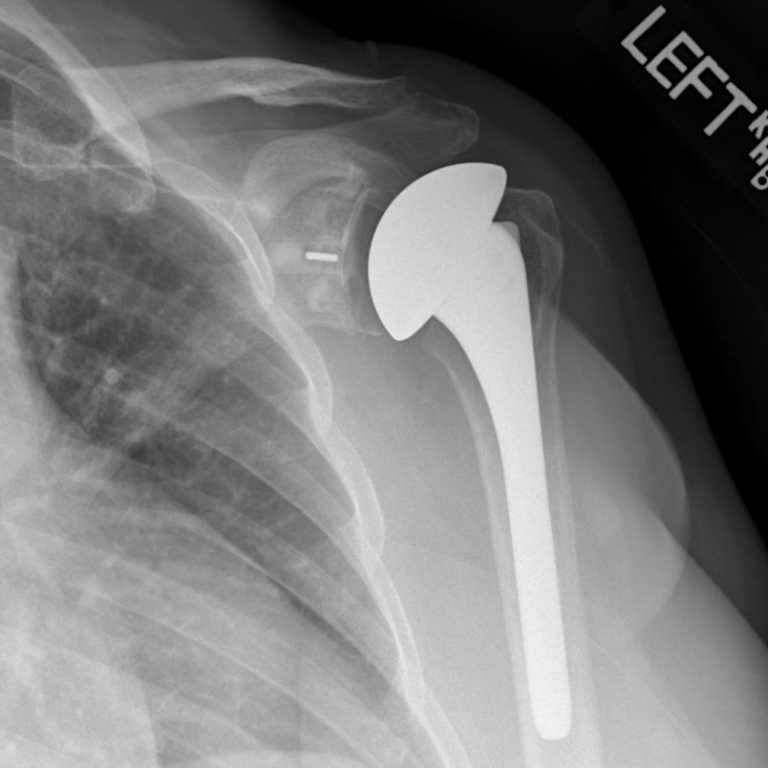

Standard (Anatomic) Total Shoulder Replacement | Dr. Gordon Groh

Partial or Total Shoulder Replacement | Dr Skedros Orthopaedics

Shoulder X Ray post Operation – Radiology Imaging

The imaging examination after surgery. (A) X-ray of the left shoulder …

Shoulder Surgery Austin, TX | Rotator Cuff Repair Cedar Park | Round Rock

Reverse Shoulder Replacement FAQ’s – Kyle McClintock, DO | Shoulder and …

GALLERY – Seacoast Shoulder